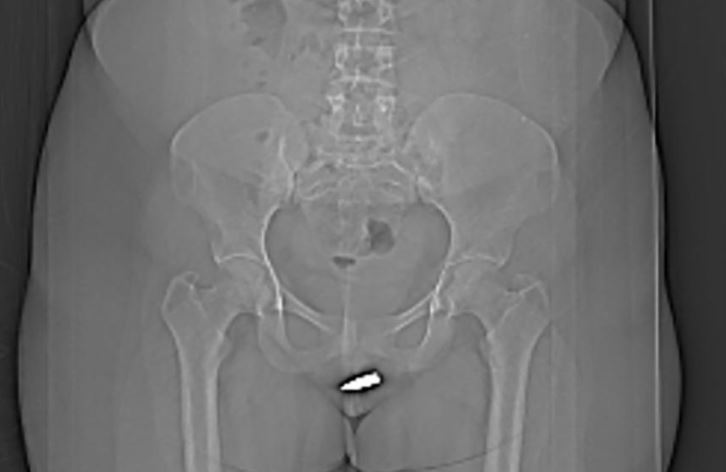

Η γυναίκα φέρεται να χαλάρωνε στο σπίτι της όταν χτυπήθηκε από την αδέσποτη σφαίρα. Η περίπτωσή της αναφέρεται στο International Journal of Surgery Case Reports και η εικόνα από την ακτινογραφία φαίνεται σαν η γυναίκα να έχει κάνει piercing, στην συγκεκριμένη περιοχή. «Από όσο γνωρίζουμε, αυτός είναι ο πρώτος παράξενος τραυματισμός από σφαίρα που διεισδύει στην περιοχή του αιδοίου (το εξωτερικό μέρος των γυναικείων γεννητικών οργάνων) και η σφαίρα συγκρατείται σφαίρα στην κλειτορίδα», έγραψαν οι συγγραφείς της μελέτης.

Σύμφωνα με τη μελέτη, η 24χρονη άγνωστη ασθενής χαλάρωσε στο σπίτι της, όταν ξαφνικά μια αδέσποτη σφαίρα πέρασε από το ταβάνι της και τη χτύπησε στα γεννητικά όργανα. Αιμόφυρτη η γυναίκα πήγε στο νοσοκομείο Ερντογάν στο Μογκαντίσου, όπου μια αξονική τομογραφία αποκάλυψε ότι το βλήμα είχε κολλήσει μέσα στην κλειτορίδα της. Από όσο γνώριζαν οι συγγραφείς της μελέτης, αυτή ήταν η πρώτη τέτοια περίπτωση.

(Φωτό: International Journal of Surgery Case Reports)